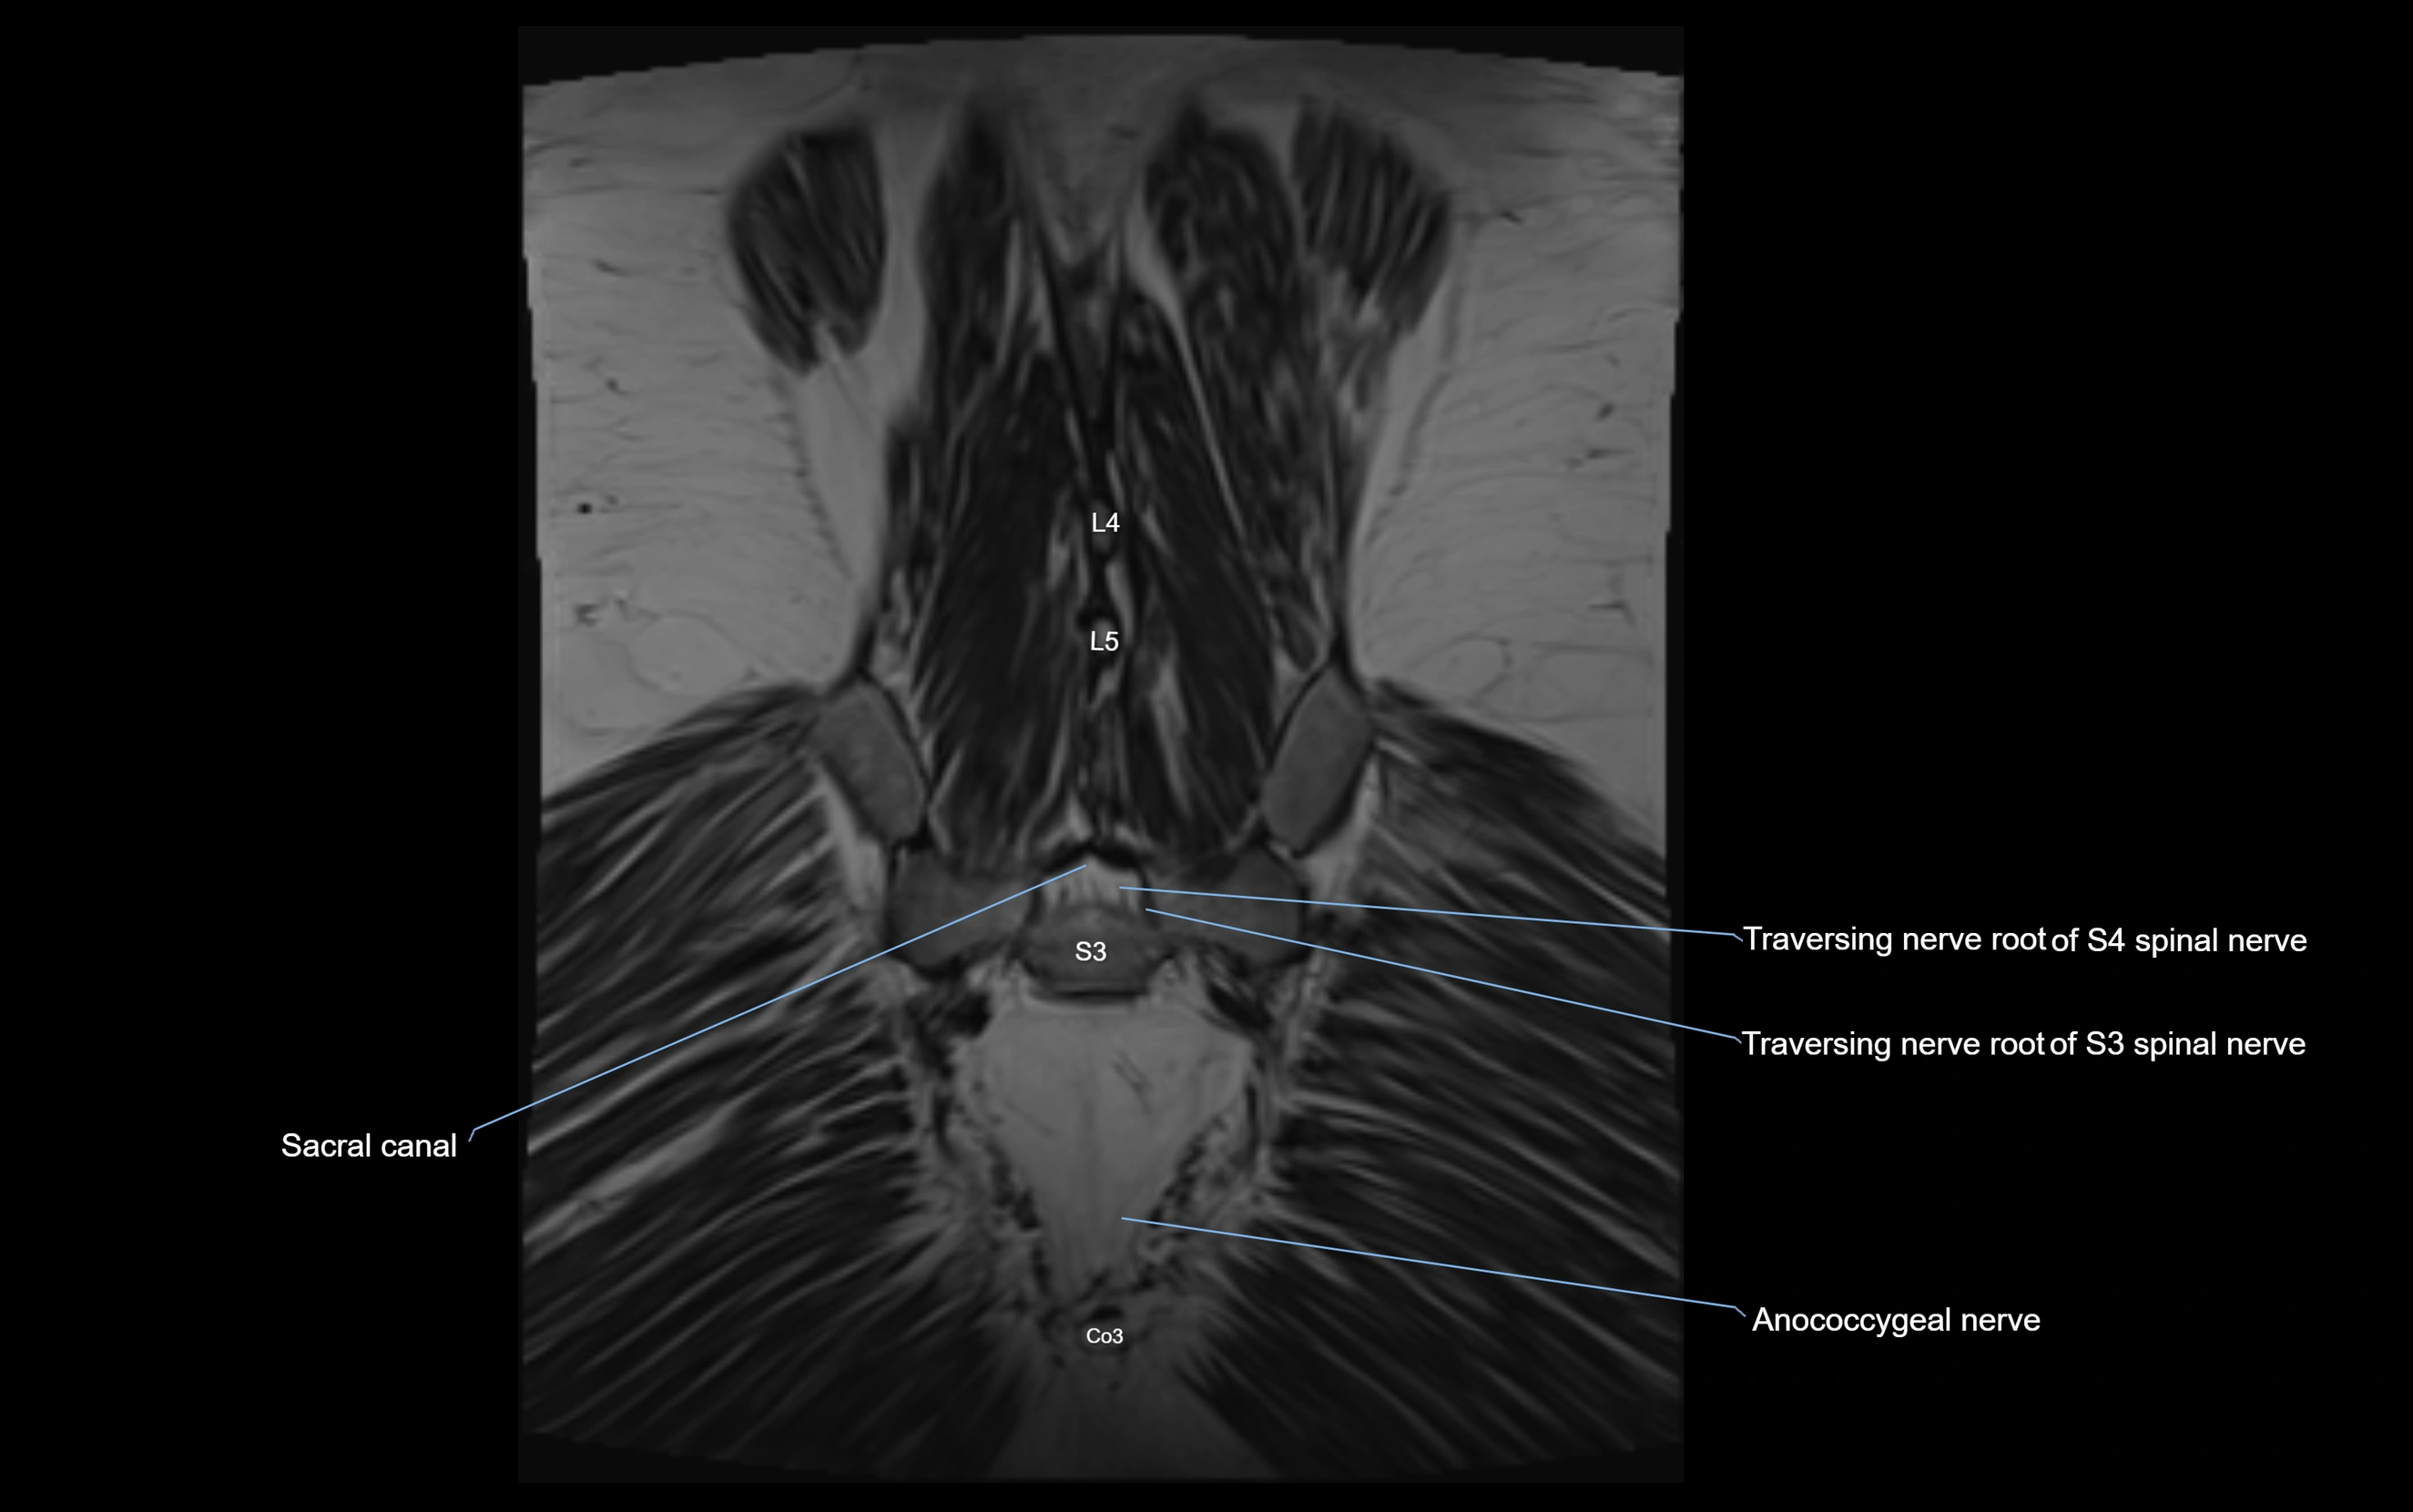

Anococcygeal nerve

The anococcygeal nerve is a small sensory nerve derived from the coccygeal plexus, which itself is formed by the ventral rami of S4, S5, and the coccygeal nerve (Co1). Although tiny, this nerve plays an important role in supplying the skin of the coccyx and the area between the anus and coccyx. It passes through the sacrotuberous ligament and runs in the midline behind the coccyx.

Despite its small size, the anococcygeal nerve is clinically important because of its involvement in coccygodynia (coccyx pain) and perineal pain syndromes.

MRI Appearance

3D T2 SPACE / CISS:

• Nerve appears intermediate to mildly hyperintense compared to muscle

• Surrounded by bright fat or CSF, improving visualization

• Best sequence for mapping small pelvic nerves such as the anococcygeal

MRI image

image